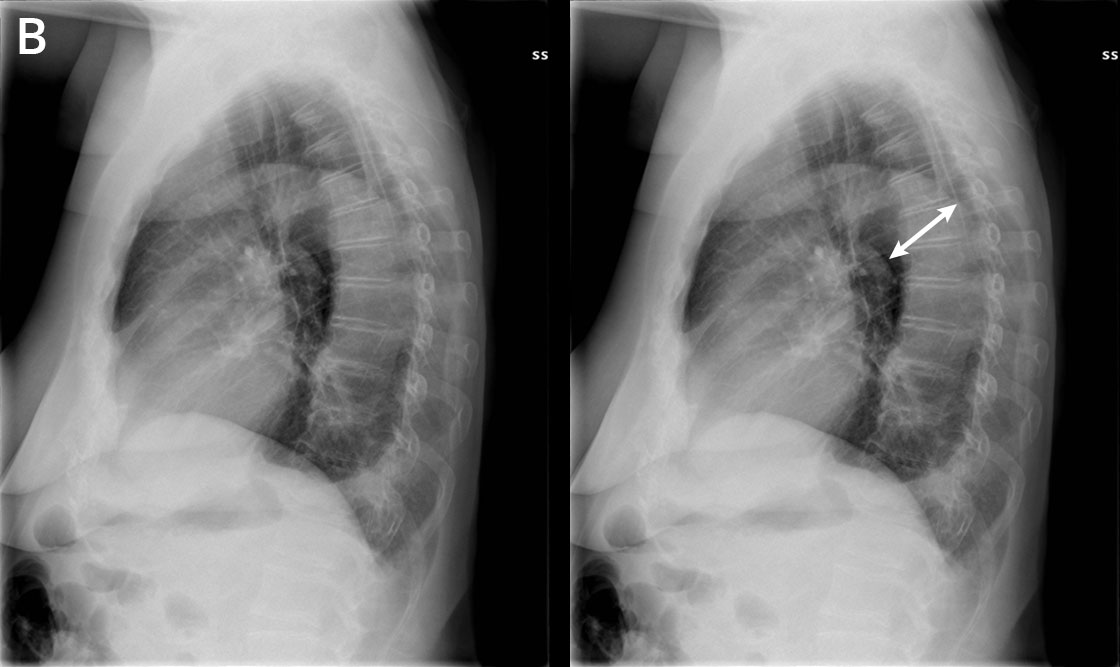

Aortan dissekoituma keuhkokuvassa (etukuva ilman löydösmerkintöjä).

Keski-ikäinen nainen tuli vastaanotolle yhtäkkiä alkaneen terävän selkäkivun vuoksi. Verenpaine oli koholla.

Aortan dissekoituma keuhkokuvassa (etukuva löydösmerkinnöin).

AP-kuvassa on nähtävissä leventynyt välikarsina. Potilaalla oli B-tyypin aortan dissekoituma. Vasemmalla hieman pleuranestettä.